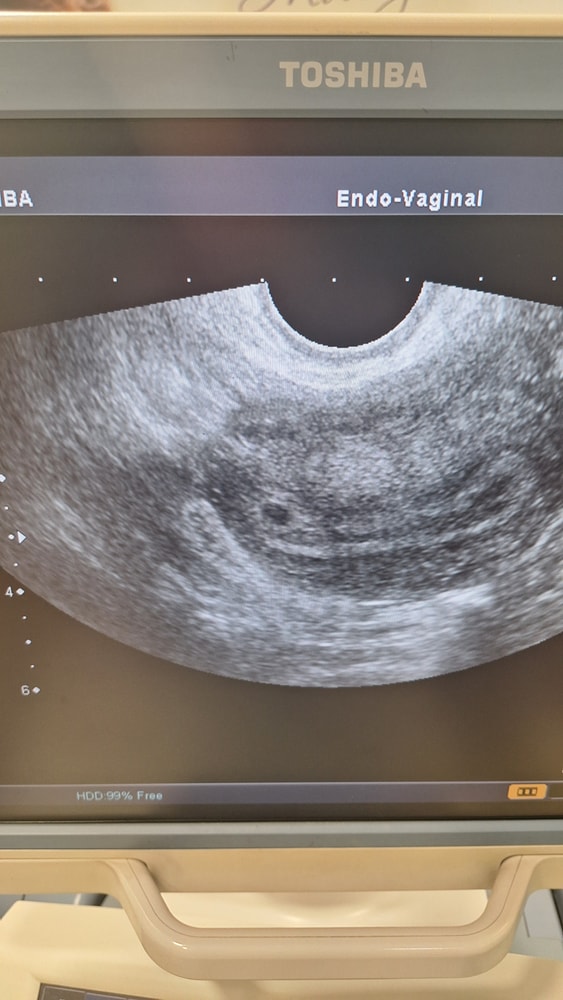

Девочки, беременность очень долгожданная. Последние месячные были 04.02.2025. Половой акт последний был 15.02. Хгч рос очень плохо. Последний от 17.03- 3386. По узи матки: " В верхней трети в правом углу анэхогенное образование с гиперэхогенным ободоком 3.7 мм. Беременность малого срока ? На узи прийти через неделю. Я так понимаю плодное яйцо намного меньше срока?

Нормально может все быть, для того и нужна динамика по узи. Вот судя по таблице оно должно быть 5мм при вашем уровне хгч 3300. А по доверительному интервалу, так вообще может быть и 4мм. и растёт она примерно 1 мм в день. Так что может и нагонит